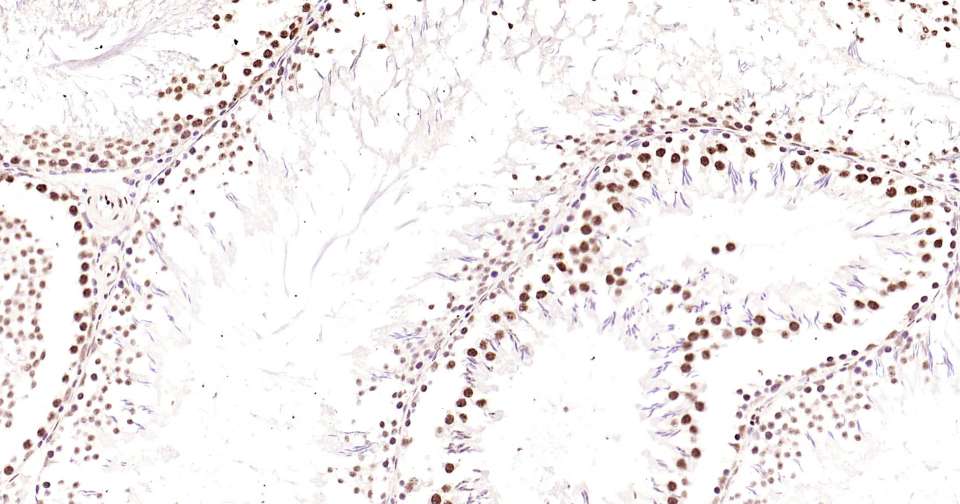

Immunohistochemical analysis of paraffin embedded rat testis tissue slide using IHC0345R (Rat Phospho-CREB-1 (Ser133) Kit).